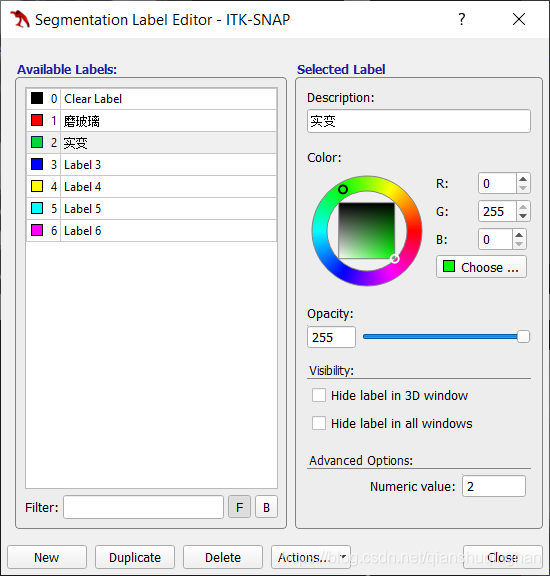

设置和导入导出标签

从菜单栏Segmentation->Label Editor进入如下界面,可手动修改label命名、从而更直观。

通过Actions,可以保存和导入自定义的label模板